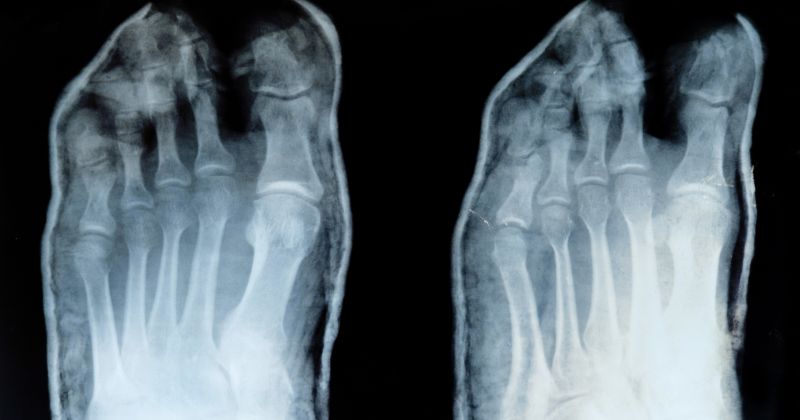

In una radiografia del piede sano, le ossa appaiono ben allineate, con margini netti e una struttura regolare. Gli spazi articolari sono uniformi, senza segni evidenti di restringimento o erosione. Anche i tessuti molli – seppur meno visibili – non presentano segni di gonfiore anomalo, calcificazioni o lesioni.

L’obiettivo di questa indagine è proprio quello di fornire un punto di riferimento per distinguere un’anatomia normale da una che presenta alterazioni. È qui che diventa utile conoscere la radiografia del piede sotto carico, spesso usata per condizioni come l’alluce valgo o il piede piatto.

Se nella radiografia si notano fratture, deformità, riduzione degli spazi articolari, o segni di artrosi, è importante approfondire con un professionista. Alcune delle patologie più comuni rilevabili tramite RX sono: